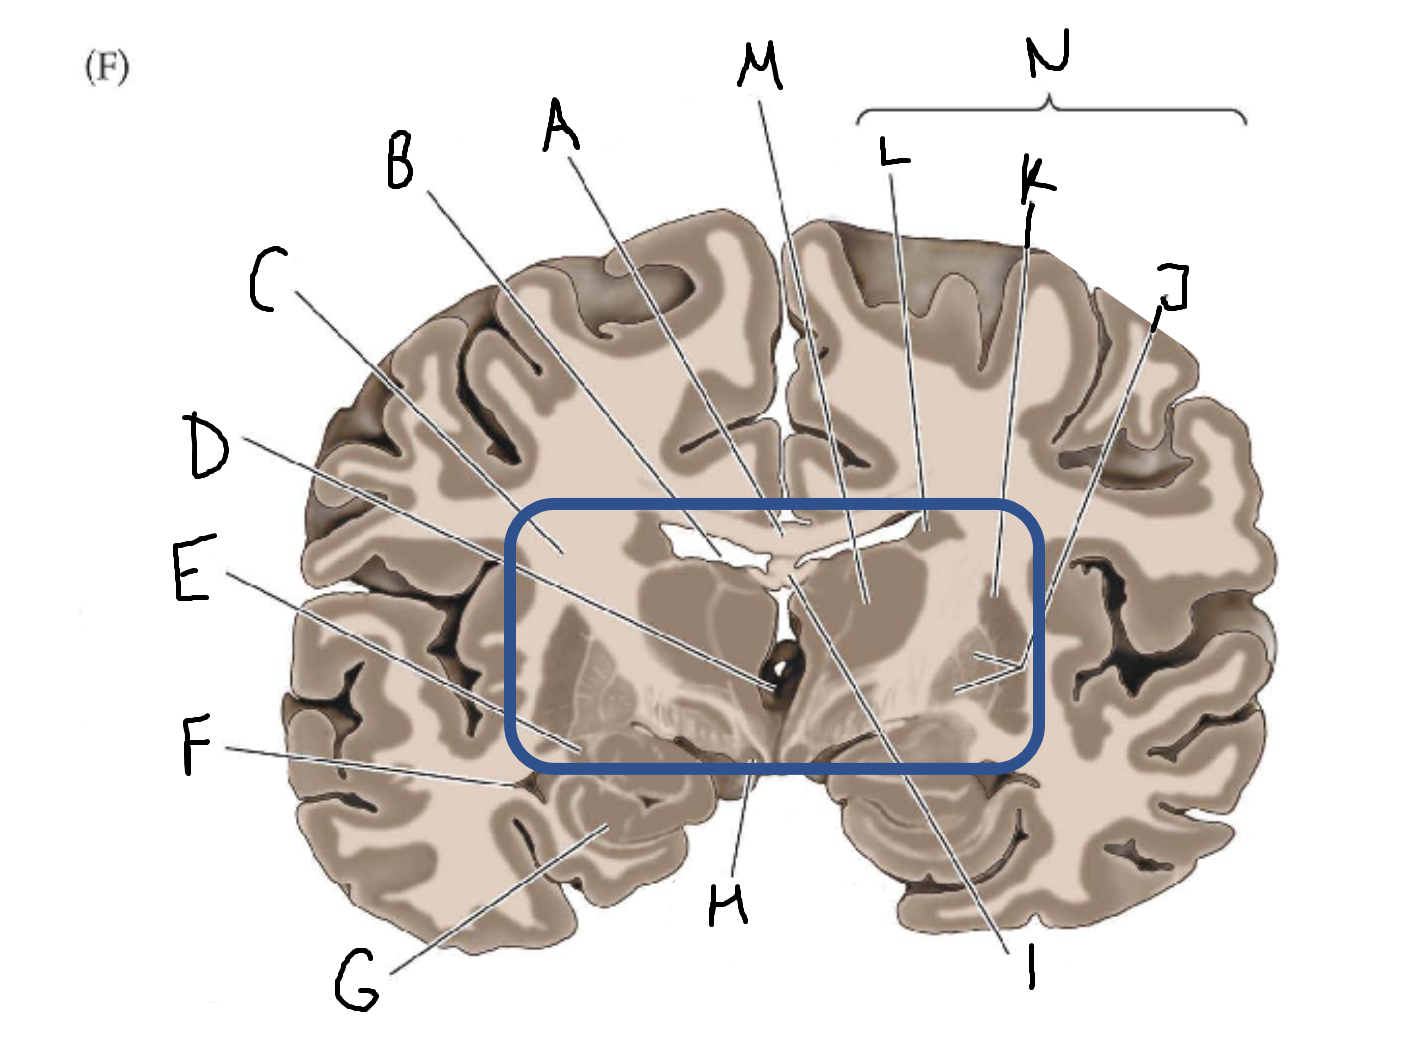

A

corpus callosum

B

lateral ventricle

C

internal capsule

D

third ventricle

E

tail of caudate nucleus

F

lateral ventricle

G

hippocampus

H

mammillary body

I

fornix

J

globus pallidus

K

putamen

L

caudate

M

thalamus

N

basal ganglia